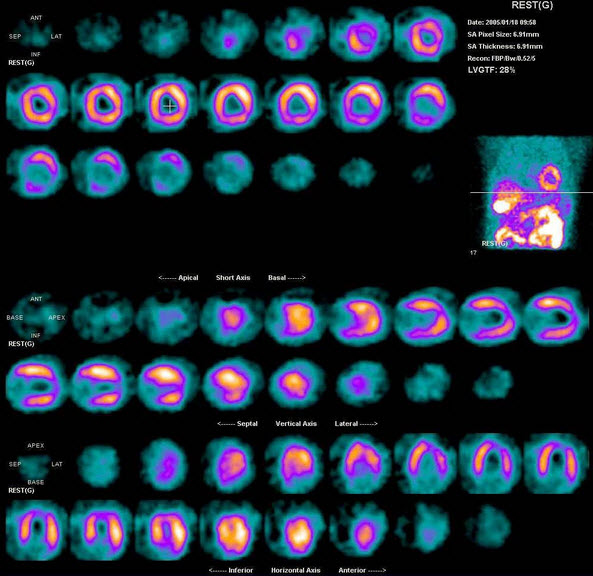

79、多项选择题

男性,53岁,反复胸闷10年。查体:心界扩大。行Tc-MIBI静息心肌灌注显像如图,可能的诊断是()

A.扩张型心肌病

B.左心室心尖、部分前壁、侧壁缺血

C.缺血型心肌病

D.肥厚型心肌病

E.大致正常的影像